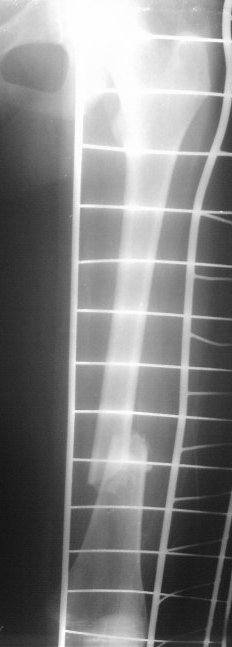

На сегодняшний день вот такая картина: девочка, 13 лет, 3 недели на скелетном вытяжении по поводу оскольчатого перелома нижней трети левого бедра.

Сейчас инфекцию "победили", отек бедра за последние дни значительно спал, но имеется укорочение 2 см, отломки уже "прихватились",патологической подвижности нет.

Добрый вечер!Такое впечатление,что система постоянного скелетного вытяжения не работала,какой был груз по оси?Стояние отломков неудовлетворительное,дополнительно обследовать и принимать решение оперативного лечения,попробуйте добавить груз по оси, если растяните, можно и ВО ЧКО по Илизарову.И конечно выбор антибиотика.Удачи!

Да, скелетное вытяжение тут как-то не сработало так как хотелось бы. Груз 6 кг (вес 45 кг). Сейчас уже, видимо, расчитывать на вытяжение не приходится, т.к. мозоль начала формироваться и подвижность исчезла.

Это снимки при поступлении, похоже.

Я бы сделал свежие. Пока предполагаю, что раз срок большой, возраст маленький, то, вероятно, лучше в два этапа - - аппаратом растянуть за неделю, а потом заштифтовать. Раз старше 12 лет, то согласен с Марком, не TENами, а нетолстым ригидным стержнем с латерализованным проксимальным отделом. Зона роста если и пострадает, то всего одна, и за оставшейся период роста не успеет сформироваться разница длин.